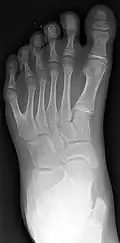

Classification is performed by using x-ray imaging to see the bone structures.[17] In 1961, Frantz and O'Rahilly proposed that congenital anomalies of the limb could be classified in seven categories, based on the embryonic failure causing the clinical presentation. These categories are failure of formation of parts, failure of differentiation, duplication, overgrowth, undergrowth, congenital constriction band syndrome, and generalized skeletal abnormalities.[36] In 1976 this was modified by Swanson.[37] Polydactyly belongs to the category of duplication.[12] As of 2009, research has shown that the majority of congenital anomalies occur during the 4-week embryologic period of rapid limb development.[12]

Right-sided duplication of the right little toe in an 8.5 months old male, with two toes (fifth and sixth) apparently forming joints with the fifth metatarsal bone, which is mildly broadened distally. The duplicated toes have almost normal growth. The fifth toe has mild varus angulation, and the sixth toe has substantial valgus angulation. -